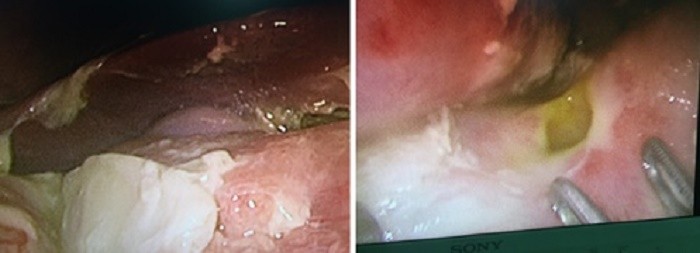

Hình ảnh lỗ thủng và giả mạc

Các bác sĩ khoa Ngoại Nhi đã tiến hành phẫu thuật nội soi kết hợp truyền máu hồi sức cho cháu bé. Ghi nhận tổn thương trong quá trình phẫu thuật có 01 lỗ thủng tại mặt trước của hành tá tràng kích thước khoảng 0.7 x 0.7 cm, bờ lỗ thủng mềm, dễ rách, kèm theo nhiều giả mạc, dịch đục trong ổ bụng. Bệnh nhi  đã được phẫu thuật nội soi khâu lỗ thủng hành tá tràng, lau rửa sạch ổ bụng. Sau 7 ngày điều trị tại khoa Ngoại nhi, toàn trạng trẻ ổn định, ăn uống bình thường đã  được xuất viện.